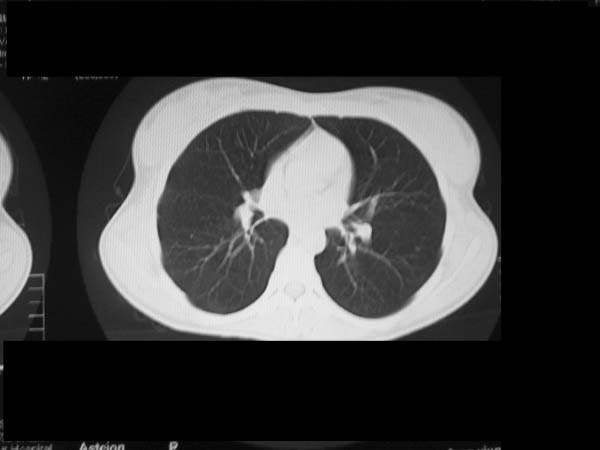

标题: CT13486:F 17Y 咳嗽 咳痰数日请会诊 [打印本页]

标题: CT13486:F 17Y 咳嗽 咳痰数日请会诊

白细胞9600不发烧

考虑右下结核球

右肺下叶结核灶

右下肺背段病灶,考虑结核与炎症鉴别,请进一步检查.

考虑结核球,建议治疗后复查

结核与肿瘤同时考虑

右下肺外基段病灶,考虑炎症,建议治疗后复查,以排外结核

考虑为:右肺下叶外基底段结核球。

结果;痰中找到结核杆菌

痰涂片已找到结核杆菌  将结果告诉大家